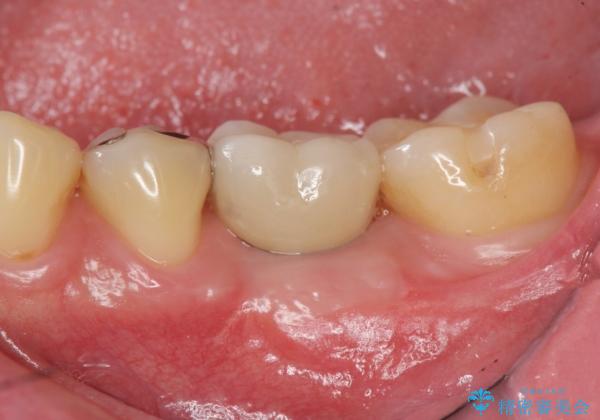

- 銀歯が揺れる、噛むと痛い、と治療を希望され来院されました。

銀歯・レジンコアを除去したところ、薄い残存歯質に亀裂が入り、保存が難しい状況が認められました。

歯を残すことが難しい状況であることの説明、抜歯の提案を行い、抜歯後はブリッジ・入れ歯ではなくインプラント治療を希望されました。